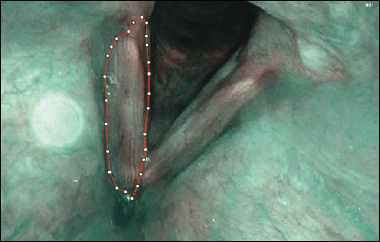

The entire frame selection and annotation process was conducted using our custom-built platform, which enabled cloud-based access to all frames stored in the central database, automated selection of informative frames from endoscopic videos, and seamless in-platform annotation capabilities. Using our system for segmenting videoendoscopic frames, we delineated the papilloma area involved before the first operation, and during follow-up visits in both WL and NBI (Cover figure and Fig. 1). We then calculated the average coverage from multiple frames per patient, both during the initial visit and at follow-up (Fig. 2).

In detail, the delineation procedure utilised in the current study consisted of: (1) a clinical expert selecting informative frames from a set chosen by the AI – at least 10 to be annotated (resident annotating first, then a specialist correcting, if needed); (2) the papilloma annotation process, i.e., delineating where the papilloma is visible in the given frame; (3) annotating the left and the right VFs separately (Cover figure, Figs. 1-2). Subsequently, the data were processed by data scientists and AI specialists. This way, the information from the images annotated by the medical experts could be used to calculate an objective, quantitative measure of the coverage of a VF by papillomas.

The implementation of the GC-AID method created by the authors is a web application (NBI-ML system) that allows to upload and process videos from the videolaryngoscope. In this system, the AI model selects the most informative frames from the video with a visible glottis, adequate definition, and no blurring, overexposure, or limited visibility. With this tool, medical experts can conveniently perform segmentations and share results, which ultimately reduces the time required for data synchronisation, annotation standardisation, and VF segmentation in both healthy larynges and those affected by RRP (Cover figure and Fig. 1). Moreover, the entire procedure is highly standardised, meaning that experts performing annotation have exactly the same set of available classes of annotation/segmentation to choose from. In the current article, a very precise description of an algorithm to calculate the VF coverage with papilloma was provided. In a broader context, such an approach can also be applied to other types of laryngeal pathologies covering different parts of the glottis. We believe that creating standardised procedures and tools for laryngeal videoendoscopic frame annotation and segmentation is one of the key challenges when creating large-scale databases of consistent information on laryngeal pathologies for the development of AI models in laryngology.

Figure 1. Endoluminal annotation of a vocal fold in narrow band imaging modality of a frame extracted from videos obtained during laryngoscopy. The outline of annotation for the right vocal fold is shown.